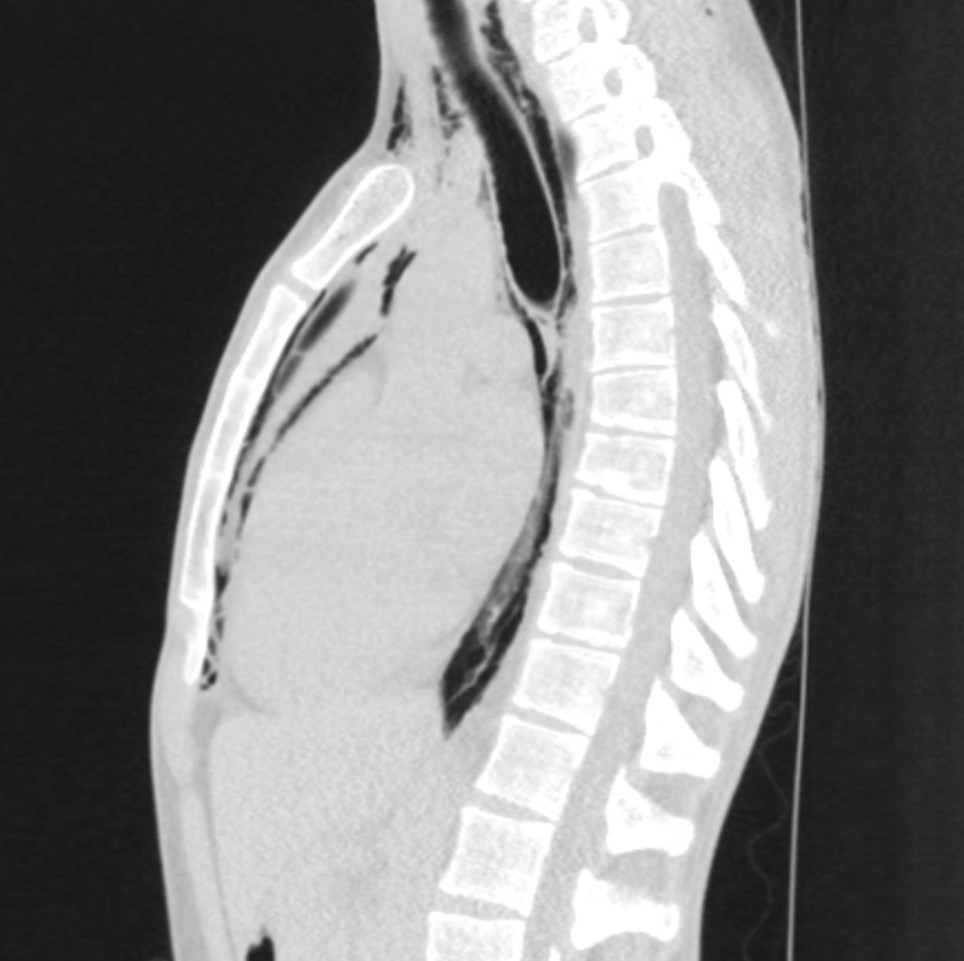

Røntgenbildet er tatt av en mann i 20-årene som fikk akutte brystsmerter med ledsagende dyspné mens han befant seg i ro. Smertene strålte ut til begge skuldre og rygg og ble forverret ved inspirasjon. Han hadde stabile vitale parametere og normale blodprøver.

Røntgen thorax viste luft i bløtvevet på halsen og supraklavikulært bilateralt, langs trachea, hjertet og langs aortakonturen lateralt. CT thorax uten intravenøs kontrast bekreftet pneumomediastinum og utelukket pneumothorax. Ved kontroll etter tre uker var pasienten smertefri, og røntgen thorax viste fullstendig regress av pneumomediastinum.